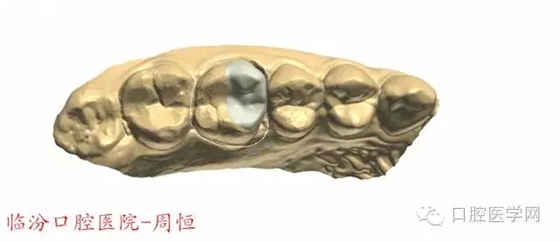

圖4 牙體預(yù)備前咬頜觀